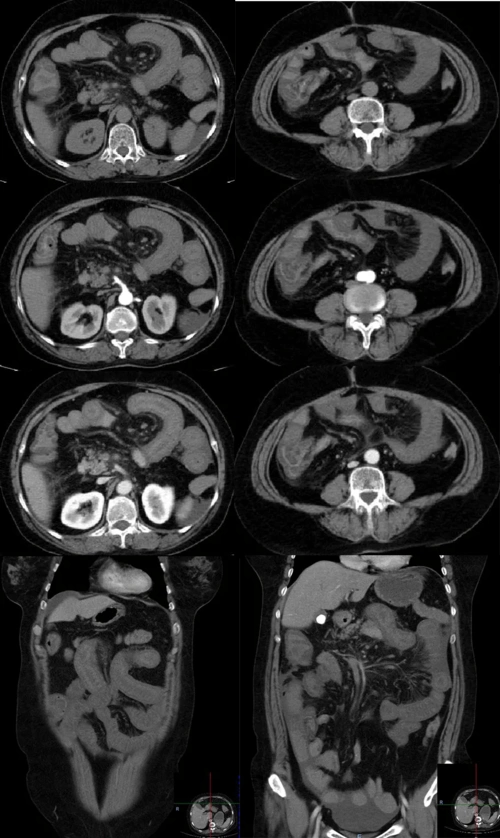

房颤患者的噩梦之不一样的急性腹痛肠系膜上动脉栓塞

急性腹痛病因之肠系膜上动脉栓塞